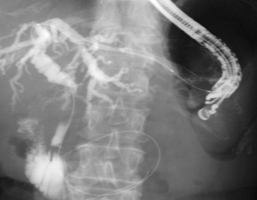

実際の症例をお示します。患者さんは膵癌により胆管が詰って黄疸が出現しました。膵癌が十二指腸へ広がり内腔が狭くなったため、内視鏡が通過せず、通常のERCPによるステント留置が不可能でした。そのためEUS-BDを施行しました。胃内から超音波内視鏡で肝臓の中の胆管を観察して、胆管を穿刺します(図1)。胆管に造影剤を満たし(図2)、ガイドワイヤーを挿入し、胆管金属ステントを留置しました(図3,4)。この手技により、体内にチューブを埋め込む形で胆汁の流れを確保することができ、黄疸は改善しました。

図3図3

図4図4